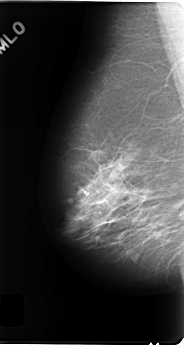

C_0177_1.RIGHT_MLO